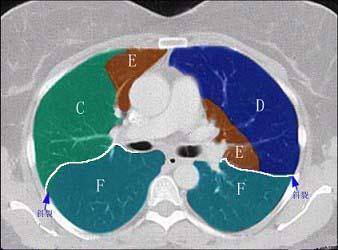

问题 结合肺段模式肺动脉干与右肺动脉层面肺动脉干与右肺动脉层面、心室层面、主动脉弓层面、 左右心房层面(如图),选出左肺上叶的组成 ( )

选项 A.A+B B.A+B+C C.A+B+C+D D.A+B+C+D+E E.A+B+C+D+E+F

答案 D